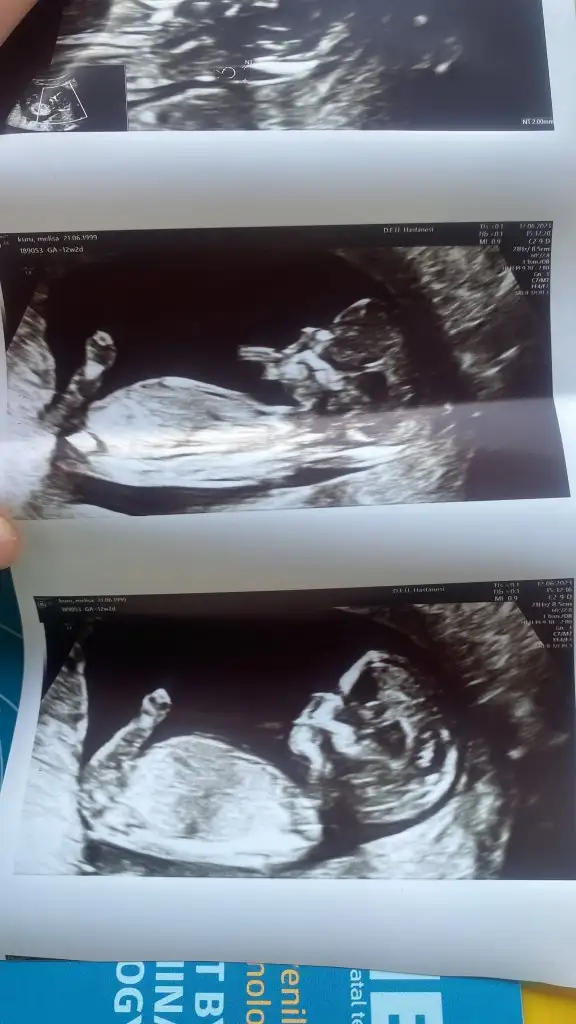

M MELOME Üye Kayıtlı Üye 13 Nisan 2023 48 15 8 26 13 Haziran 2023 Konu Sahibi Konu Sahibi MELOME #1 Merhabalar 12 haftalık görüntümüz tahminleri alabilir miyim lütfen lütfen Eklentiler 577A6434-81A1-4515-ADAF-43A78A27EAB6.webp 30,3 KB · Görüntüleme: 84 540A51BC-4ED1-4C3E-8555-8572660B8A06.webp 32,3 KB · Görüntüleme: 86

lunamovas GECE her şeyi karartsa bile AY'I karartamazdı… Kayıtlı Üye 30 Kasım 2022 1.166 416 53 36 13 Haziran 2023 Konu Sahibi Konu Sahibi MELOME #2 MELOME .!.: Merhabalar 12 haftalık görüntümüz tahminleri alabilir miyim lütfen lütfen Genişletmek için tıkla... Kız gibi duruyor. Ama değişebilir. 12 hafta erken bir hafta cnm

M MELOME Üye Kayıtlı Üye 13 Nisan 2023 48 15 8 26 13 Haziran 2023 Konu Sahibi Konu Sahibi MELOME #3 lunamovas .!.: Kız gibi duruyor. Ama değişebilir. 12 hafta erken bir hafta cnm Genişletmek için tıkla... Doktor da %90 üstü inde kız dedi bakalım ya çok heyecanlıyım

lunamovas GECE her şeyi karartsa bile AY'I karartamazdı… Kayıtlı Üye 30 Kasım 2022 1.166 416 53 36 13 Haziran 2023 Konu Sahibi Konu Sahibi MELOME #4 MELOME .!.: Doktor da %90 üstü inde kız dedi bakalım ya çok heyecanlıyım Genişletmek için tıkla... Banada 12 haftada %90 denildi . Sonra 13 ve 16 da kesin kız dedi